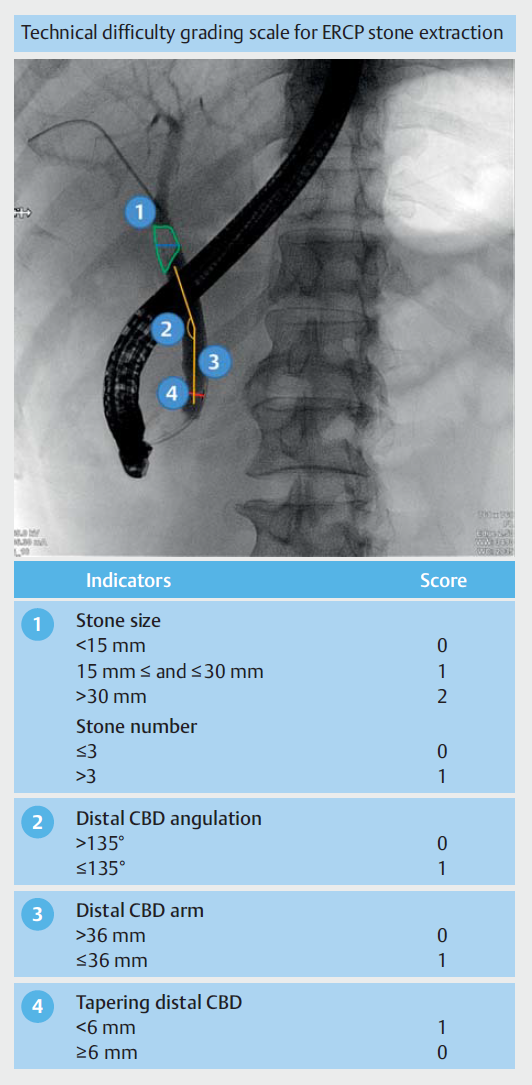

开发和更新了一个由三个模块组成的CAD系统。模块1负责结石、CBD、十二指肠镜的分割,并为后续测量模块提供基础。模块2接收来自模块1的像素级分割结果,测量结石尺寸、结石数量、远端CBD直径、远端CBD臂、远端CBD角度和十二指肠镜直径,远端CBD角度定义为沿CBD病程从壶腹口开始的第一个角度,远端CBD臂定义为远端CBD角度点与壶腹口之间的长度(以毫米为单位),十二指肠镜直径(11.3 mm)作为将参数单位从像素转换为毫米的标尺(图1)。模块3接收来自模块2的测量结果,并根据ERCP取石的技术难度分级量表将其分配给技术难度分数(图2)。

图2. ERCP取石技术难度分级量表。